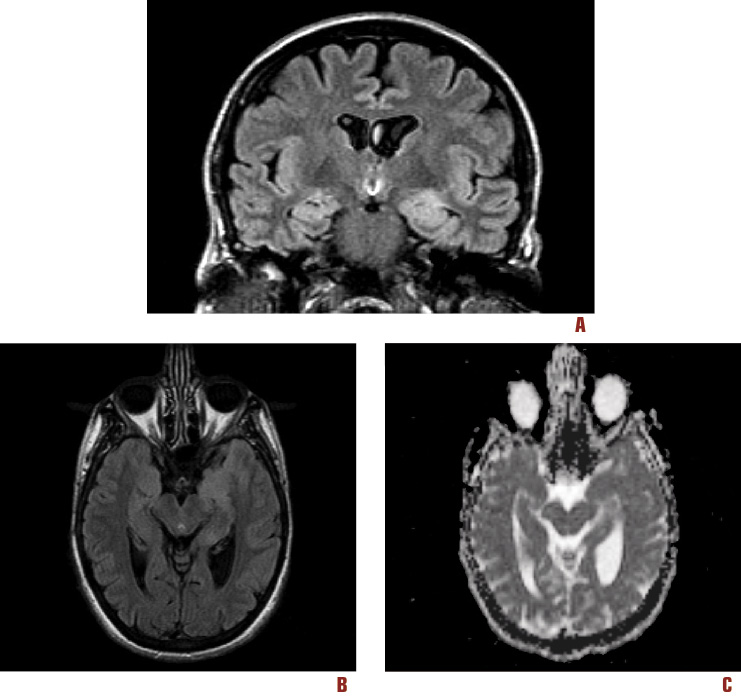

Un ulteriore episodio critico, con caratteristiche simili, è stato registrato mediante l’EEG dinamico ambulatoriale. L’esame RM encefalo ha mostrato, nelle immagini T2-FLAIR, un’iperintensità di segnale a carico del complesso nucleare amigdala-testa del nucleo dell’ippocampo a sinistra. Le strutture apparivano tumefatte, ma non erano presenti captazioni patologiche di contrasto. Concomitavano invece modesti dismorfismi cerebrali congeniti, tra cui un ampliamento del trigono ventricolare sinistro, con aspetto bombato, e una posizione bassa delle amigdale cerebellari (Chiari 0). La mappa del coefficiente ADC non mostrava anomalie (Figura 2). L’esame del liquido cefalo-rachidiano non mostrava alterazioni della cellularità, né delle proteine, né la presenza di sintesi intratecale di Ig. Le sierologie per sifilide, HIV-1 e HIV-2, HSV-1 e HSV-2, HHV-6, EBV, CMV e Borrelia Burgdorferi risultavano nella norma. Le ricerche dei comuni marcatori tumorali, degli anticorpi onco-neurali (anti-Hu, -Yo, -Ri, -Ma2, -CV2, -anfifisina) e degli anticorpi anti-Gad risultavano negative.

Figura 2. RM – 1.5T; (A) Scansione T2 – FLAIR coronale, (B) scansione T2 – FLAIR assiale e (C) mappa del coefficiente apparente di diffusione (ADC). Nelle immagini in T2 – FLAIR si evidenzia un aumento dell’intensità di segnale a carico del complesso nucleare amigdala-testa del nucleo dell’ippocampo a sinistra. Tali strutture appaiono tumefatte, ma non presentano captazioni patologiche di contrasto. Concomitano modesti dismorfismi cerebrali congeniti, tra cui un ampliamento del trigono ventricolare sinistro, con aspetto bombato, e una posizione bassa delle amigdale cerebellari (Chiari 0). Dalla mappa ADC non appaiono invece anomalie